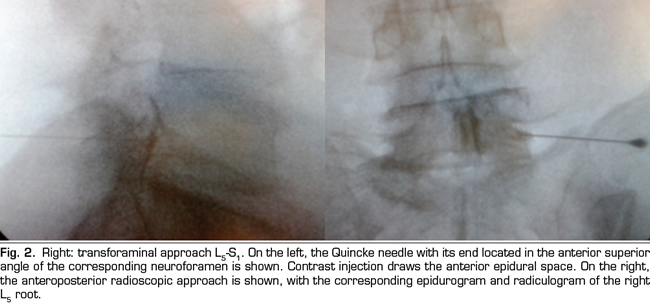

Figure 1

Figure 2